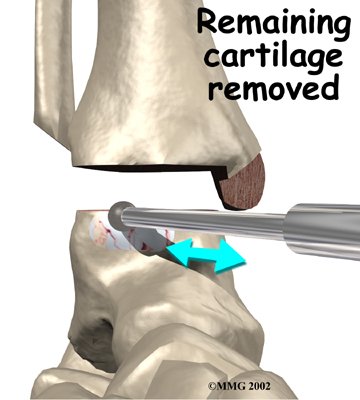

Remainder of the talar articular surface removed

Using the arthroscope to watch, other instruments are inserted into the ankle joint to remove the cartilage surface. The cartilage surface is removed using a small rotary cutting tool. Once the surfaces are prepared, screws are placed through small incisions in the skin to hold the bones together as they heal, or fuse. This procedure is not significantly different from the open procedure except that the incisions are smaller.